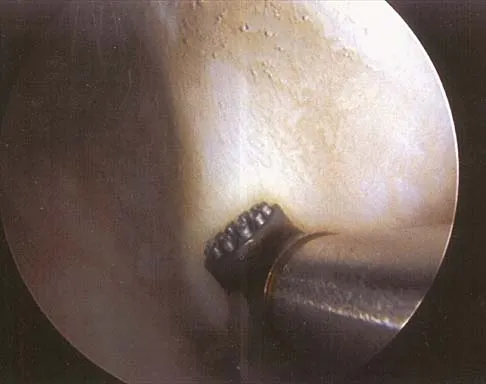

Question 22

Figure 25 shows an arthroscopic thermal capsular shrinkage device being used in the anterior inferior quadrant of a patient with a subluxating shoulder. Which of the following neurologic complications is most frequently reported with this technique?

Explanation